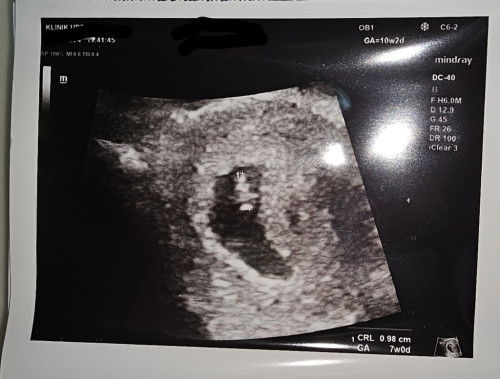

Hi mommiess!!! saja nak share sbb happy and utk mommies supaya tak overthinking 😄LMP saya 24/3. saya scan 2 minggu lepas spatutnya baby dah 8 weeks tapi masa scan tu baru 5 weeks (nampak kantung je) semalam repeat scan baby 7 weeks walaupun ikut LMP spatutnya baby 10 weeks. (nampak baby cinonet dah 👇) so nak bagitau stay positive dont worry too much ok mommies as long as baby tu ada progress everything will be okay 😘❤️